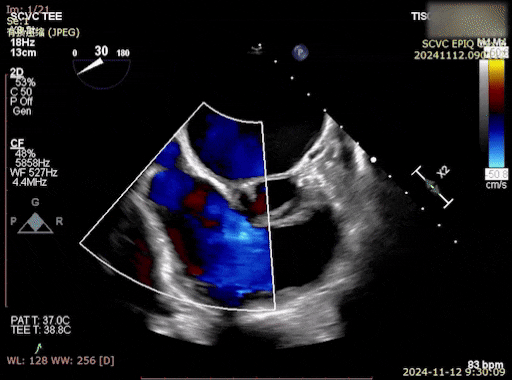

同时,基线影像学评估包括经胸超声心动图,用于明确TR严重程度、瓣叶对合情况;右心导管检查用于获取基础血流动力学数据,包括肺毛细血管楔压(PAWP)、肺动脉压(PA)、右心室(RV)及右心房(RA)压力及v波等,为术中判断和术后对比提供依据。

术前右心室造影及TEE提示三尖瓣大量反流